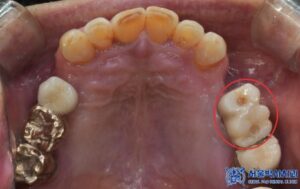

이후 상악 좌우도 순차적으로 치료를 진행하였으며,

기존 타 치과에서 심은 왼쪽 위 작은 어금니 위치의

임플란트와 파절된 인접 보철물도

함께 제거하였습니다.

상악 좌우는 모두 뼈이식을 동반한

무절개임플란트를 총 6개 식립하였습니다.

특히 맞춤형 지대주를 제작하여 음식물 끼임을

줄이고 환자 개개인의 구강구조에 꼭 맞게

보철물을 제작합니다.